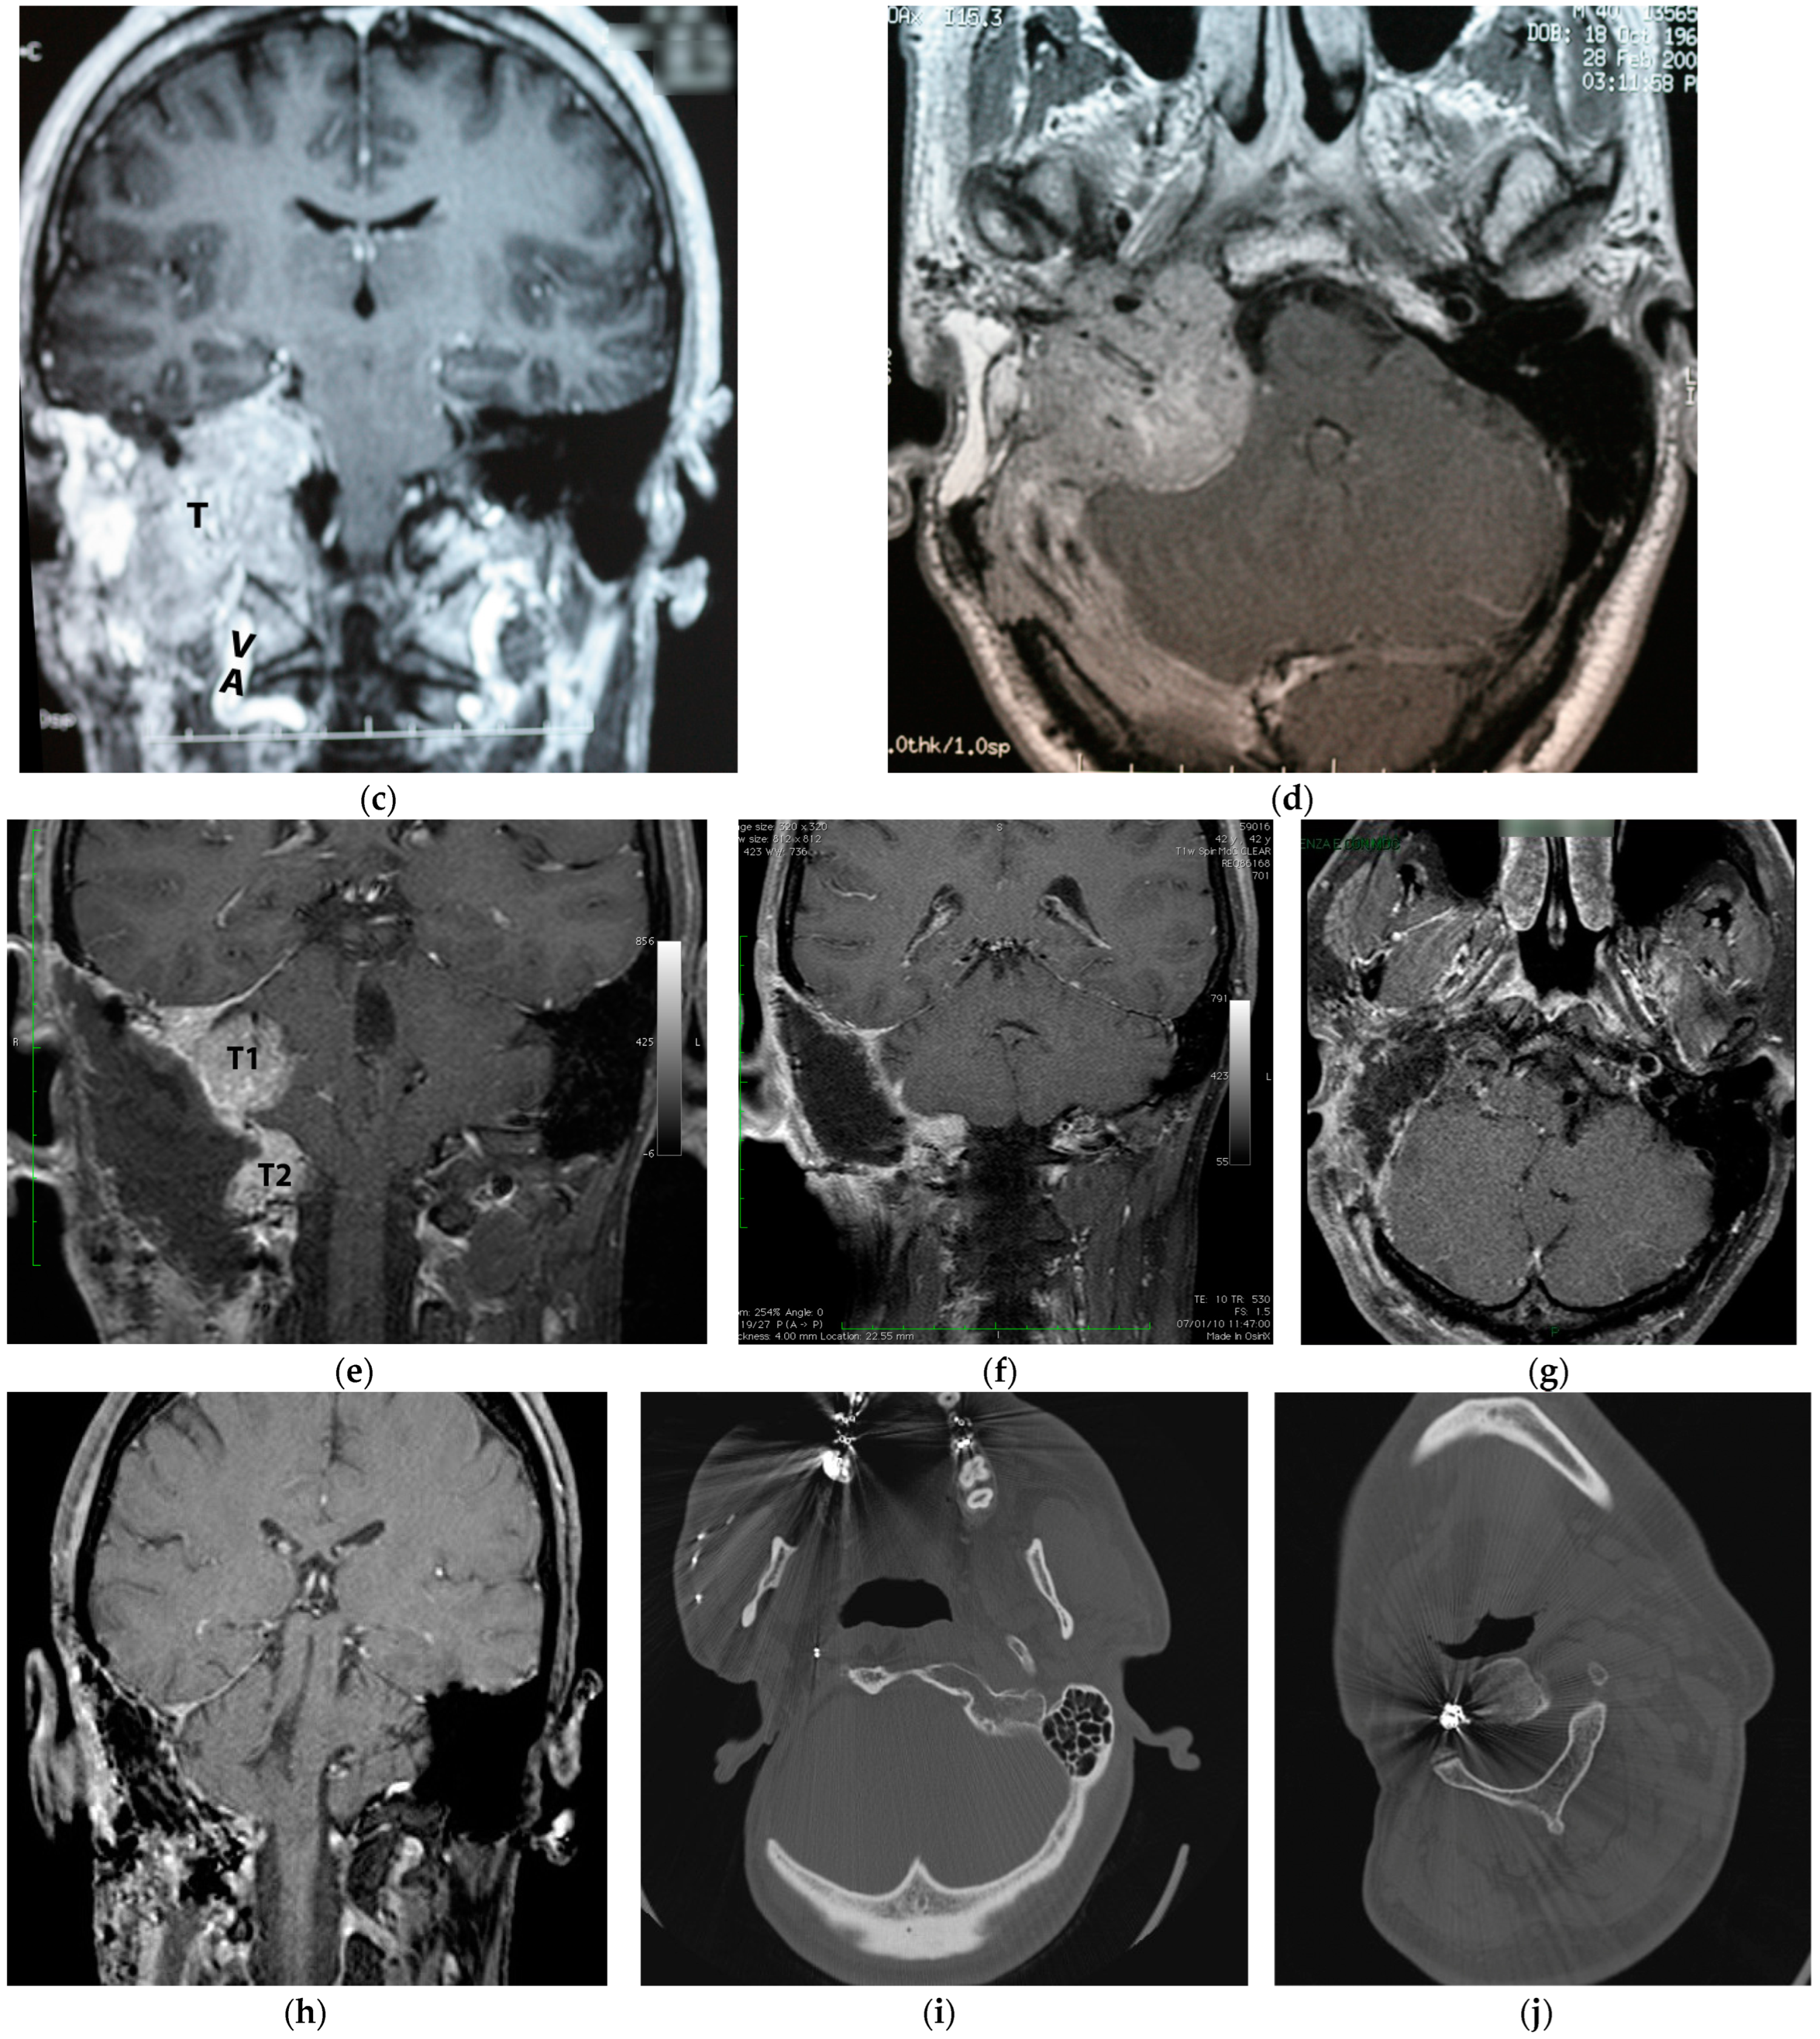

5.1. Case 1: (C4Di2)

5.2. Case 2: (C3Di1 + Stage I VP)

5.3. Case 3: (C4Di2Vi)

5.4. Case 4: (C3Di2 + Stage II Vagal PGL)

5.5. Case 5: (C3Di2Vi)

5.6. Case 6: (C4Di2Vi)